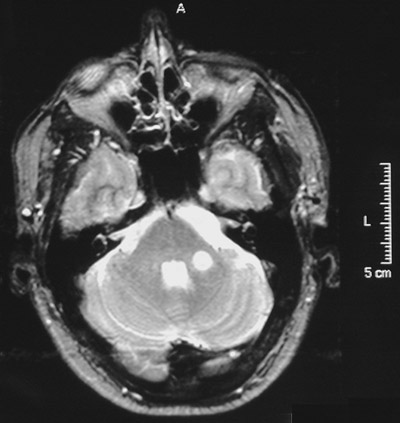

In the T2 weighted scans of the cerebrum above and the cerebellum below both demonstrate enhancing plaques of demyelination while the patient was symptomatic and having an exacerbation of his multiple sclerosis.